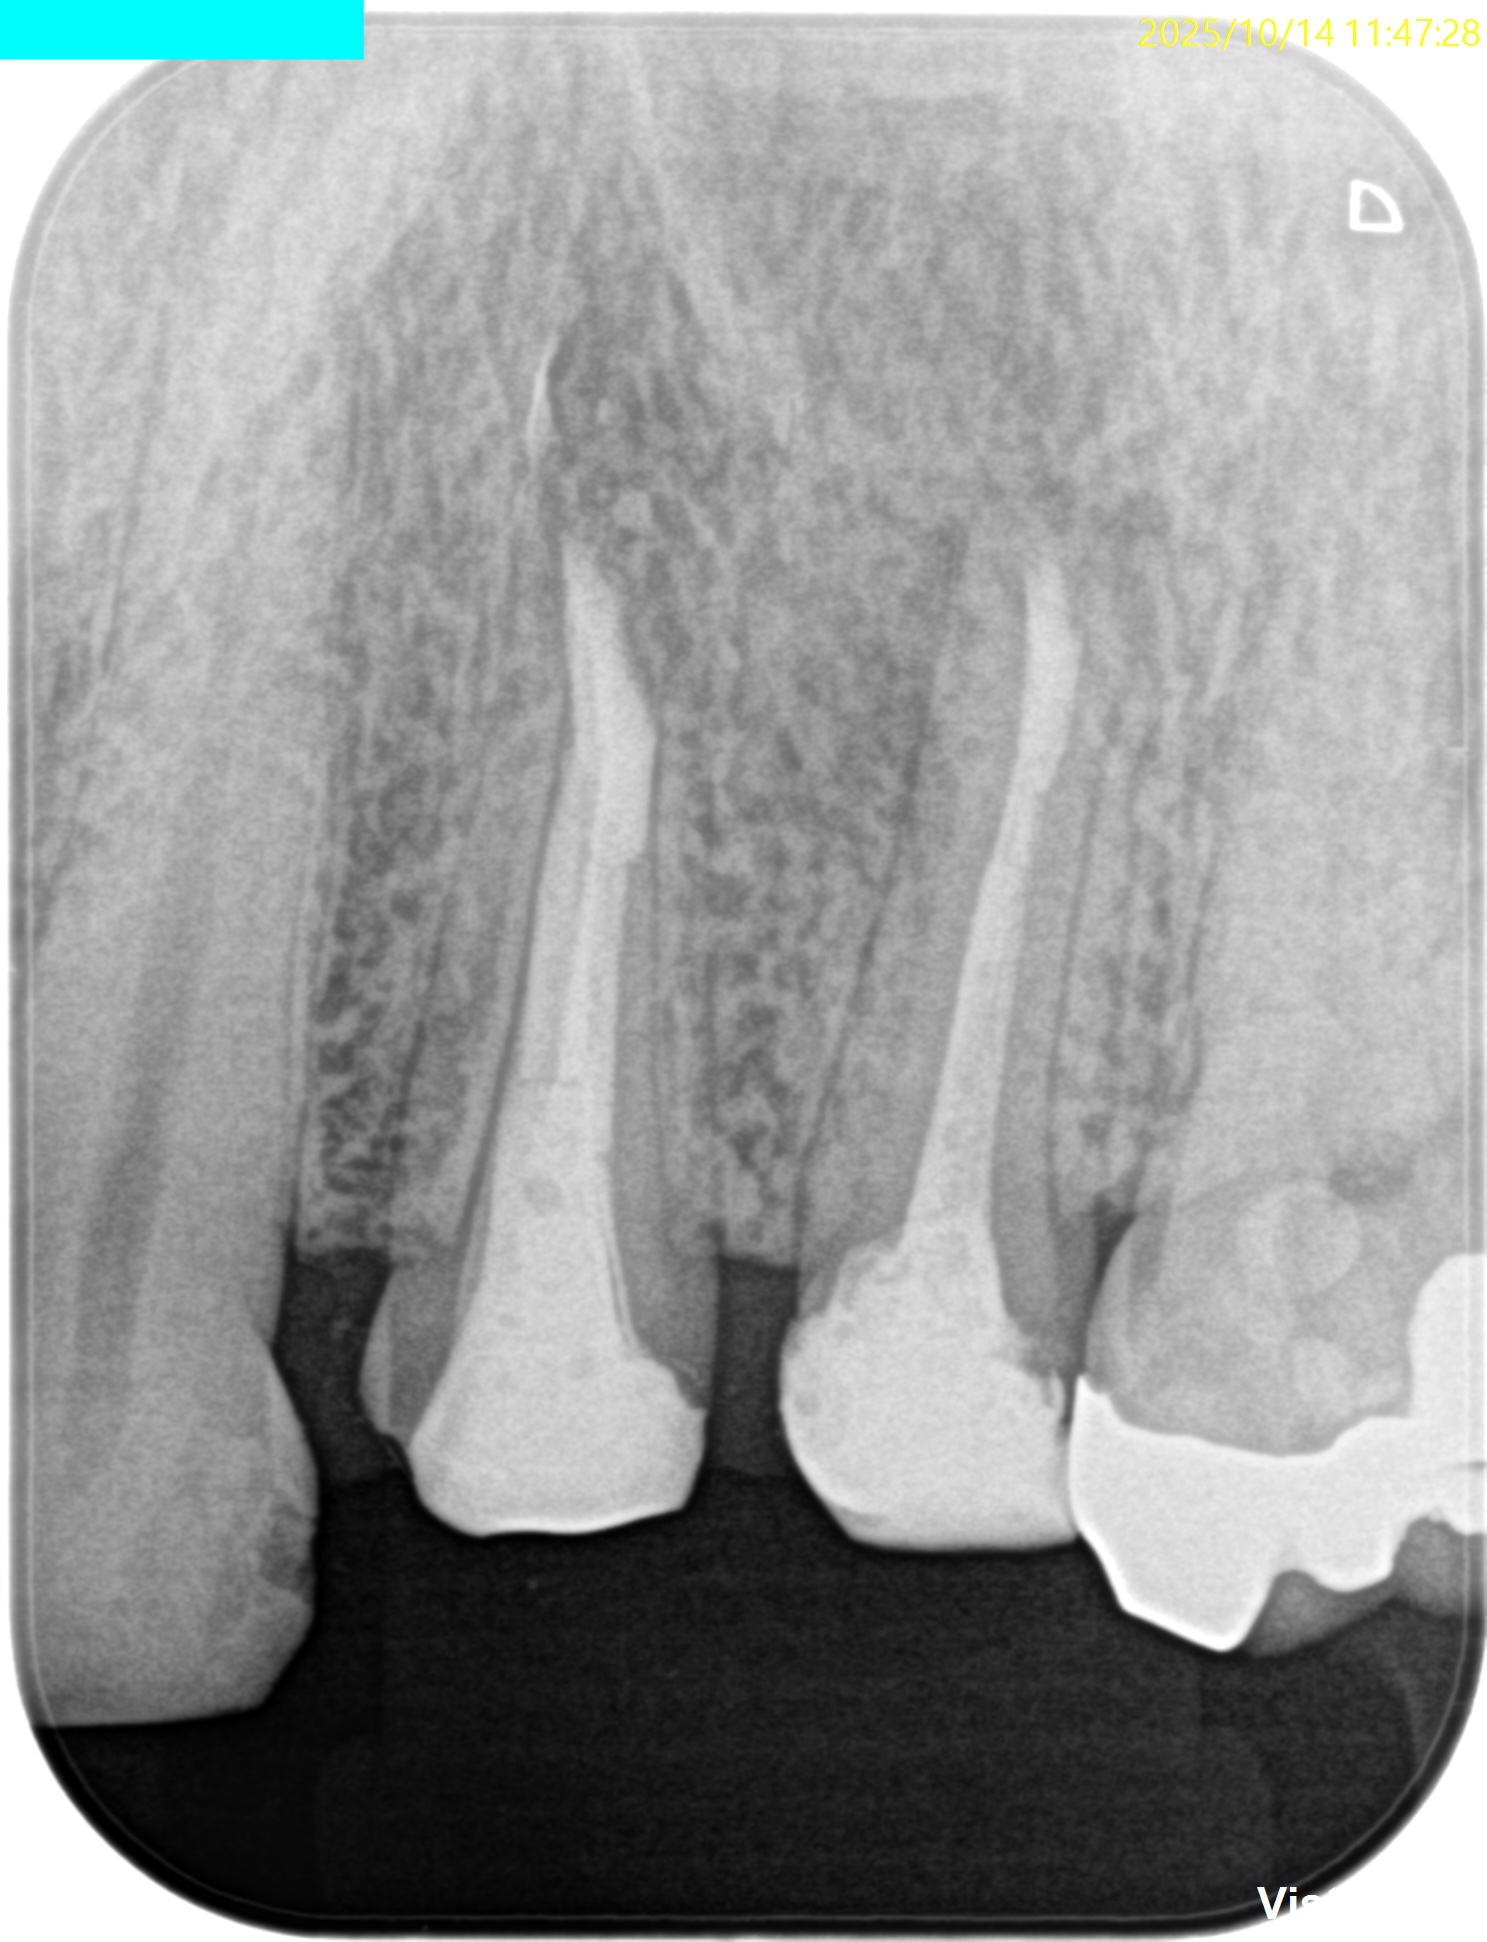

PA(2025.8.25)

#13のポストは長くテーパー型だが除去には時間を要するだろう。

術後にPA, CBCTを撮影した。

#12

#13